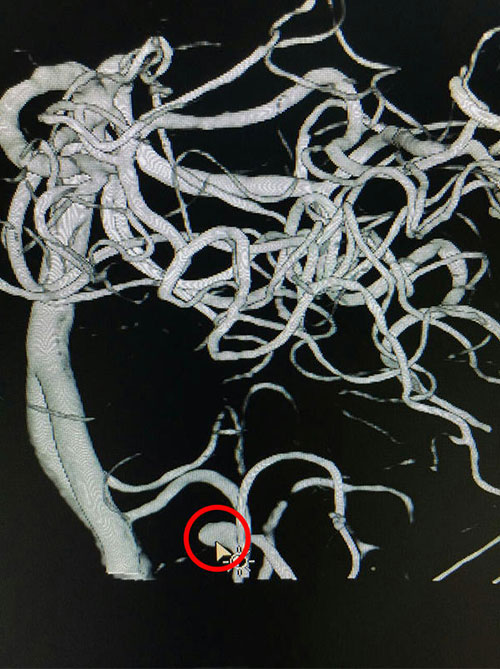

为求进一步治疗,11月22日许先生来到我院就诊,患者诉左侧肢体乏力、麻木伴吐词不清。我院神外科专家潘仁龙主任仔细诊查经后,认为患者先前脑出血诊断不明确,考虑颅脑内可能有其他问题,遂建议行全脑血管造影术检查及完善其他相关检查。11月24日DSA造影结果提示:“左小脑后下动脉瘤”,初步诊断为:1.脑干出血后遗症期;2.高血压病III级,极高危组;3.右侧面神经瘫痪。补充诊断:左小脑后下动脉动脉瘤”。

术前血管造影,红圈内箭头指向处动脉瘤瘤体